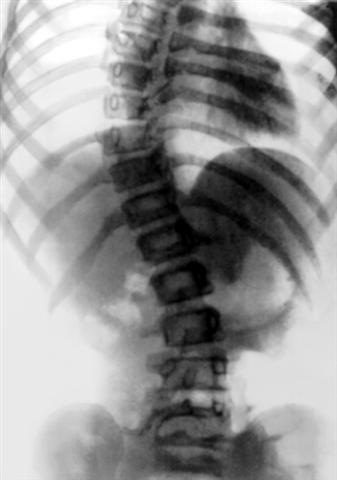

Рис. 4е). Диспластический сколиоз у девочки 12 лет: рентгенограмма позвоночника (прямая проекция) в положении больной лежа.